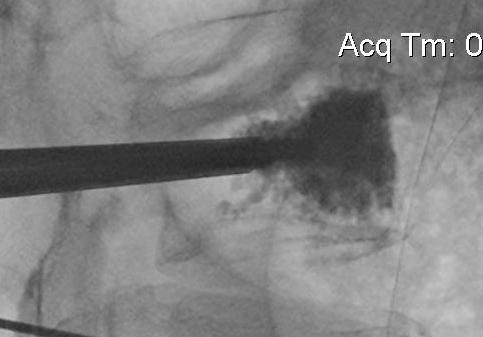

Technique

Percutaneous

- trochar into pedicle under fluoroscopy

- injection PMMA

- then inject PMMA